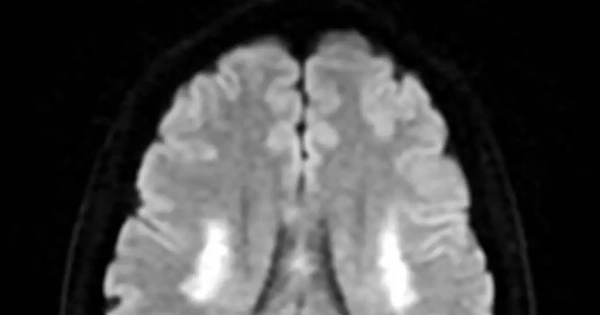

Trên hình ảnh kiểm tra, bác sĩ ghi nhận tình trạng tổn thương não xảy ra ở người bệnh (ảnh: BSCC)

PGS Huy Thắng cho biết, ngay khi nhập viện, người bệnh được chụp MRI não. Hình ảnh cho thấy tổn thương não xảy ra ở hai bên trung tâm bán bầu dục và vùng lồi thể chai. Các thăm dò mạch máu não không ghi nhận tình trạng tắc hay hẹp các động mạch lớn. Dựa trên lâm sàng và hình ảnh học, các bác sĩ chẩn đoán bệnh nhân bị nhồi máu não cấp vùng trung tâm bán bầu dục hai bên và lồi thể chai.